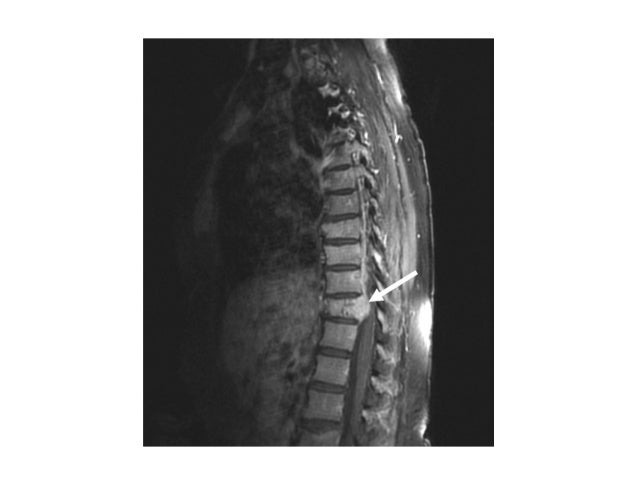

MRI of spinal cord compression in aMRI of spinal cord compression in a

women with past history of breastwomen with past hi...

24. 24. MRI of spinal cord compression in aMRI of spinal cord compression in a women with past history of breastwomen with past history of breast cancercancer